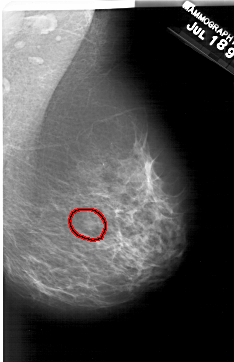

A_2001_1.LEFT_CC

LEFT_CC LINES 6106 PIXELS_PER_LINE 3631 BITS_PER_PIXEL 12 RESOLUTION 43.5 NON_OVERLAY

FILE: A_2001_1.RIGHT_CC.OVERLAY

TOTAL_ABNORMALITIES 1

ABNORMALITY 1

LESION_TYPE MASS SHAPE OVAL MARGINS OBSCURED

ASSESSMENT 2

SUBTLETY 3

PATHOLOGY BENIGN

TOTAL_OUTLINES 1

BOUNDARY